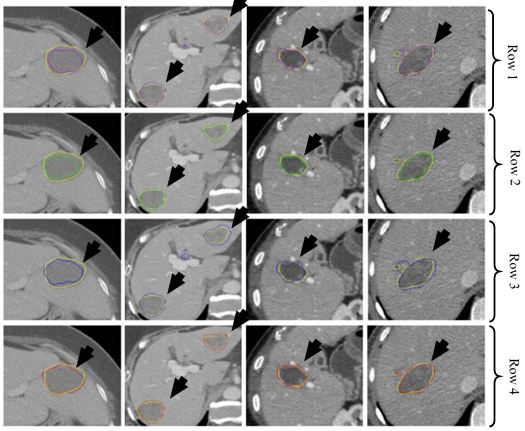

Lung cancer is a malignant disease with five year survival rate less than 20%, if not diagnosed early. Characterization of lung disease from CT images is difficult as small lung nodules are infrequently regarded malignant, difficult to biopsy and cannot be reliably characterized by positron emission tomography scan. DL-frameworks provided a new area of research in this field. In here for characterization of lung cancer (59), two DL-based frameworks are applied. Two separate characterizations were done using two DL techniques such as: CNN and DBN. It was found that CNN and DBN both gave better results than other conventional methods using feature extraction technologies. The pulmonary modules in lung could be diagnosed as malignant based on their shape which can be sphericity and speculation and composition of internal structures such as fluid, calcification and fat. In this paper, the chest CT images were collected from 1010 patients. The sensitivity of CNN and DBN was found to be 73.3% and 73.4% while specificity was found to be at 78.7% and 82.2%. The object process model of the system is given in Figure 34. The input CT images depicting various sizes of lung module is given in Figure 35. This application can be called as a ground level study of the use of DL for lung cancer detection. Multiple deeper layers could be added to improve accuracy. The paper lacked prevailing DL-based architectures.

Figure 34Characterization of CT lung cancer.

Figure 35Different sizes of lung nodules (yellow) visualized in the CT images for characterization by the CNN and DBN (reproduced with permission from (55)).